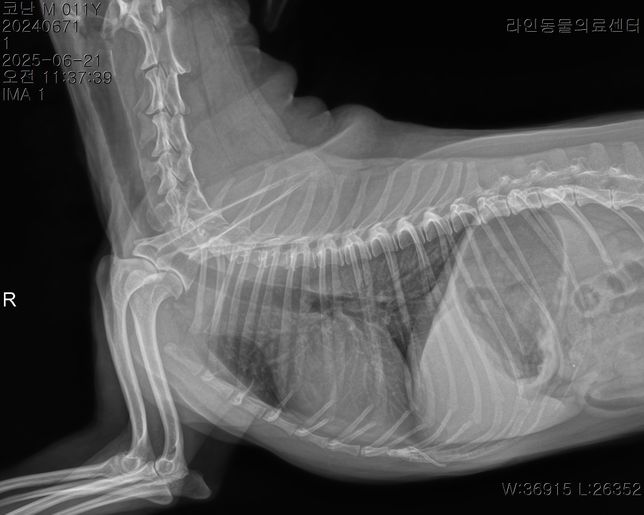

- 반려동물 건강반려동물Q. 강아지 이상증상 이유라도 좀 알고싶습니다..저희 강아지가 어제 아침부터 혀를 내밀고 과호흡에 혀가 보라색이 되고 배가 단단해지길래 바로 응급 병원에 갔더니 별다른 처치는 없었고 산소방에 30분에 있더니 배가 다시 물렁해지며 혀는 여전히 보라색이였으나 엑스레이와 호흡수가 정상이라하여 안정제/진정제 주사를 한대 맞았고 이제 안심을 하고 집에 왓는데 어제 저녁 9시경 애가 물설사와 사진처럼 점액변도 누고 밤 12시경 다시 점액변을 2차례 더 누고 새벽3시경 애가 낑낑거리며 봣더니 배가 다시 단단해져있었고 혀는 괜찮았고 호흡수만 괜찮았지만 하루 종일 잠을 못잤는데 다니던 24시 병원은 전화하니 잘 모르겠다고 솔직한 답변을 주셨고 새벽내내 이리저리 돌아만다녀서 아침에 다른 병원에 가서 엑스레이와 혈액검사 종양검사 등을 하니 저런 결과가 나왔고 이전 병원 엑스레이 사진을 보여드리니 폐침윤이 있어서 다시 엑스레이를 찍어보고 혈액검사도 해보니 심장과 폐문제는 아닌거같다 허리디스크 때문인듯하다 라고 하셨고 복부초음파는 해당 병원 장비가 갑자기 고장이 나서 되지가 않은 그런 상황입니다암은 아니라하고 특이한점은 crp 농도는 정상인데crp 는 13으로 높게 나왔습니다 오늘 찍은 엑스레이상 허리디스크가 심장과 폐 중앙 사이에 있는 허리디스크가 안좋았으며 췌장염은 리파아제 아밀라제가 괜찮다고 아닌거같다고는 하셨는데 cpLi 는 그래서 진행을 안한 상태입니다저도 강아지도 너무 지치는데요 오늘 하루종일 밥을 안먹은 상태이고 주사만 3대 진통제와 스테로이드(쿠싱상관별로없는 약한 스테로이드)를 맞은 상태입니다 대체 어떻게 해야할까요? 정말 허리디스크 때문일까요? 췌장염 가능성은 없을지 여쭤봅니다복부가 단단해지는 증상은 약 3개월전부터있었고 복명음 같은경우도 3개월전부터 있었는데 요즘은 그냥 하루종일 복명음이 들리고 소리도 점점 커지는 느낌입니다.허리디스크라 산책을 하면 안되지만 하도 애가 변을 안누길래 제가 가볍게 산책을 해주면 배가 다시 물렁해지는 그런 상황들이 여러번 있었고 2-3일전부터는 애가 식이알러지 증상도 나타났습니다 고추를 심하게 빨거나 ( 노란 고름이 나와서 항생제도 안에 넣는 세척을 오늘 진행하였고) 평상시에 포비돈으로 희석해서 멸균식염수와 같이 세척해줌에도 작년 9월부터 낫지를 않고 귀와 턱을 미친듯이 긁는 증상들도 있습니다정말 못고쳐도 좋으니 이유만이라도 좀 알고싶은데 병원에 가면 갈수록 저와 강아지는 지쳐만 갑니다한 병원에 계속 다니고 싶어도 첫번째 병원은 엑스레이만 찍고 혈액검사와 복부초음파를 요청하여도 호흡수와 엑스레이가 괜찮다고 그 어떤 처방도 받은것이 없어서 부득이하게 여러 병원들을 다니고 있는 상황인데 병원들이 가깝지도 않아서 차로 최소 1시간 거리들인 상황이라 정말 상상 이상으로 지치는데부디 혈액검사와 증상들을 살펴봐주시고 짐작이 가는 질병이나 췌장이나 대장쪽 문제는 없는지 알고싶습니다정장제와 허리디스크 약을 처방받은 상황이며 일주일동안 약을 먹어보고 그래도 이상하면 췌장이라고 들었습니다 참고로 아밀라아제 리파아제가 정상수치여도 초음파상 췌장에 에코가 있었던 이력이 있으며 심장 같은 경우는 b1 이라고 하고 청진도 잘 안들이기에 여러 병원들이 b2 는 아니라하였고 오늘 찍은 엑스레이에선 폐침윤은 없었습니다 다만 쿠싱이 살짝 의심은 된다고는 하였습니다 멏개월전에는 쿠싱검사시 cor 이 (1-6 이 정상인데 ) 인지 9 정도 나왔는데 몇개월후 오늘은 7.5 로 되었습니다 • T4-6 vertebrae의Rt. caudal articular process의defect 확인됩니다. (→)• T13-L1 vertebrae의IVDS(intervertebral disc space)가주변에비해좁게확인됩니다.(→• T13-L1 vertebrae의IVDS가주변에비해좁게확인되어IVDD 가능성고려됩니다. 신경계검사등추가적인신체검사추천되며, 신체검사상특이소견또는임상증상확인될경우척수실질평가를위한MRI 검사가추천될수있습니다.• T4-6 vertebrae의Rt. caudal articular process의dysplasia 확인되며, congenitalanomaly로고려됩니다. 이는, incidental finding으로고려되나, 척추의불안정성을야기하여IVDD를유발할수있습니다마지막 사진은 저희 강아지 작년 ct 촬영 사진입니다